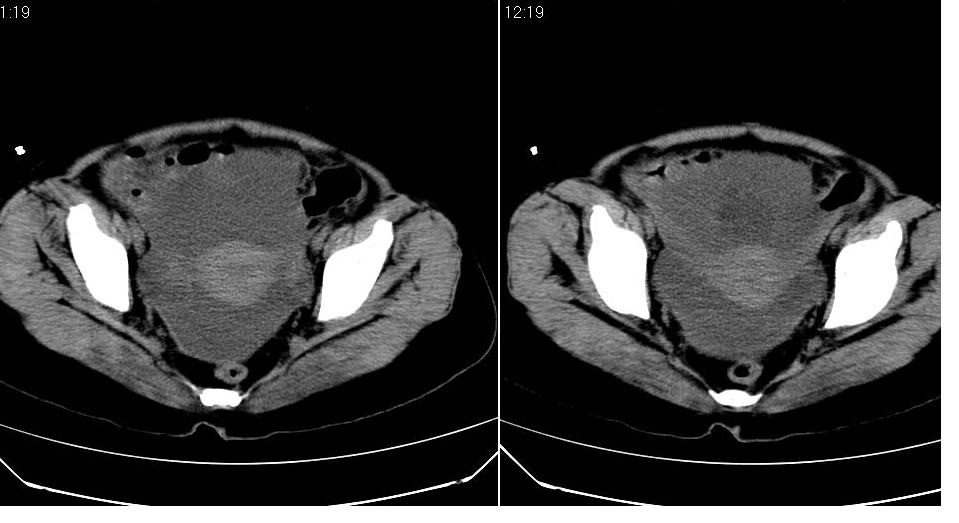

标题: CT17773B盆腔CT平扫

女 44岁,于ct17773号病例同一个病人。有结果我会尽快告诉大家。

盆腔及腹腔积液,原因待查。

结核性腹膜炎可能,